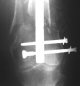

Attached are few examples from our Hospital:

A. Difficult reductions, even in retrograde nailing (my preference, easier control of "small" distal fragment) and it is much, much harder to do it anterograde (Alex, do you have one good case in your collection of anterograde nailing in very distal fractures - as you have suggested that I

should have done it in my previously posted case?

Malpositioning is much too common (recurvatum, varus - valgus).

B. Fixation loosening: distal cutting of the nail, non-unions do happen (cases attached).